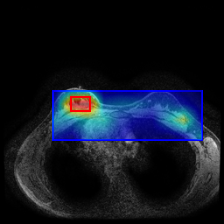

Using the trained models with state-of-the-art performance, we follow the protocol detailed in Section 2.4 and present experimental results on interpretability in Figure 3, Figure 4, and Table 3. In particular, Figure 3 illustrates several qualitative examples, while Table 3 displays pointing game accuracy and mean IoU scores. Finally, Figure 4 represents IoU distributions represented in the form of boxplots. Based on these results, we make the observations below.

Qualitative results can be misleading. In Figure 3, we present qualitative interpretability outputs for all methods considered. As can be seen, depending on the selected subset of images and the method, both accurate and inaccurate interpretability maps can be found. These findings emphasize the danger of making strong claims about interpretability methods based solely on qualitative results, including attention maps.

GradCAM interpretability for ViTs is inadequate. In both evaluation types and across multiple models, GradCAM is significantly outperformed by both attention maps and Chefer method, revealing that both methods are more appropriate for ViT interpretability compared to GradCAM, which was originally proposed for CNNs.

Attention maps show promise for interpretability. As shown in Table 3 and Figure 4, interpretability results of attention maps and the Chefer method are comparable. Attention maps generally perform better in the pointing game, while the Chefer method yields better IoU results. These observations hold true for the majority of models across all datasets, with the exception of CP-Child, where the Chefer method outperforms attention maps in the pointing game. Based on these findings, we suggest that researchers employ attention maps when the goal is to identify the most important location in an image. In other scenarios, however, we recommend using the Chefer method. In summary, while attention maps show promise, we find that the Chefer method is a more appropriate choice for interpretability in medical datasets.